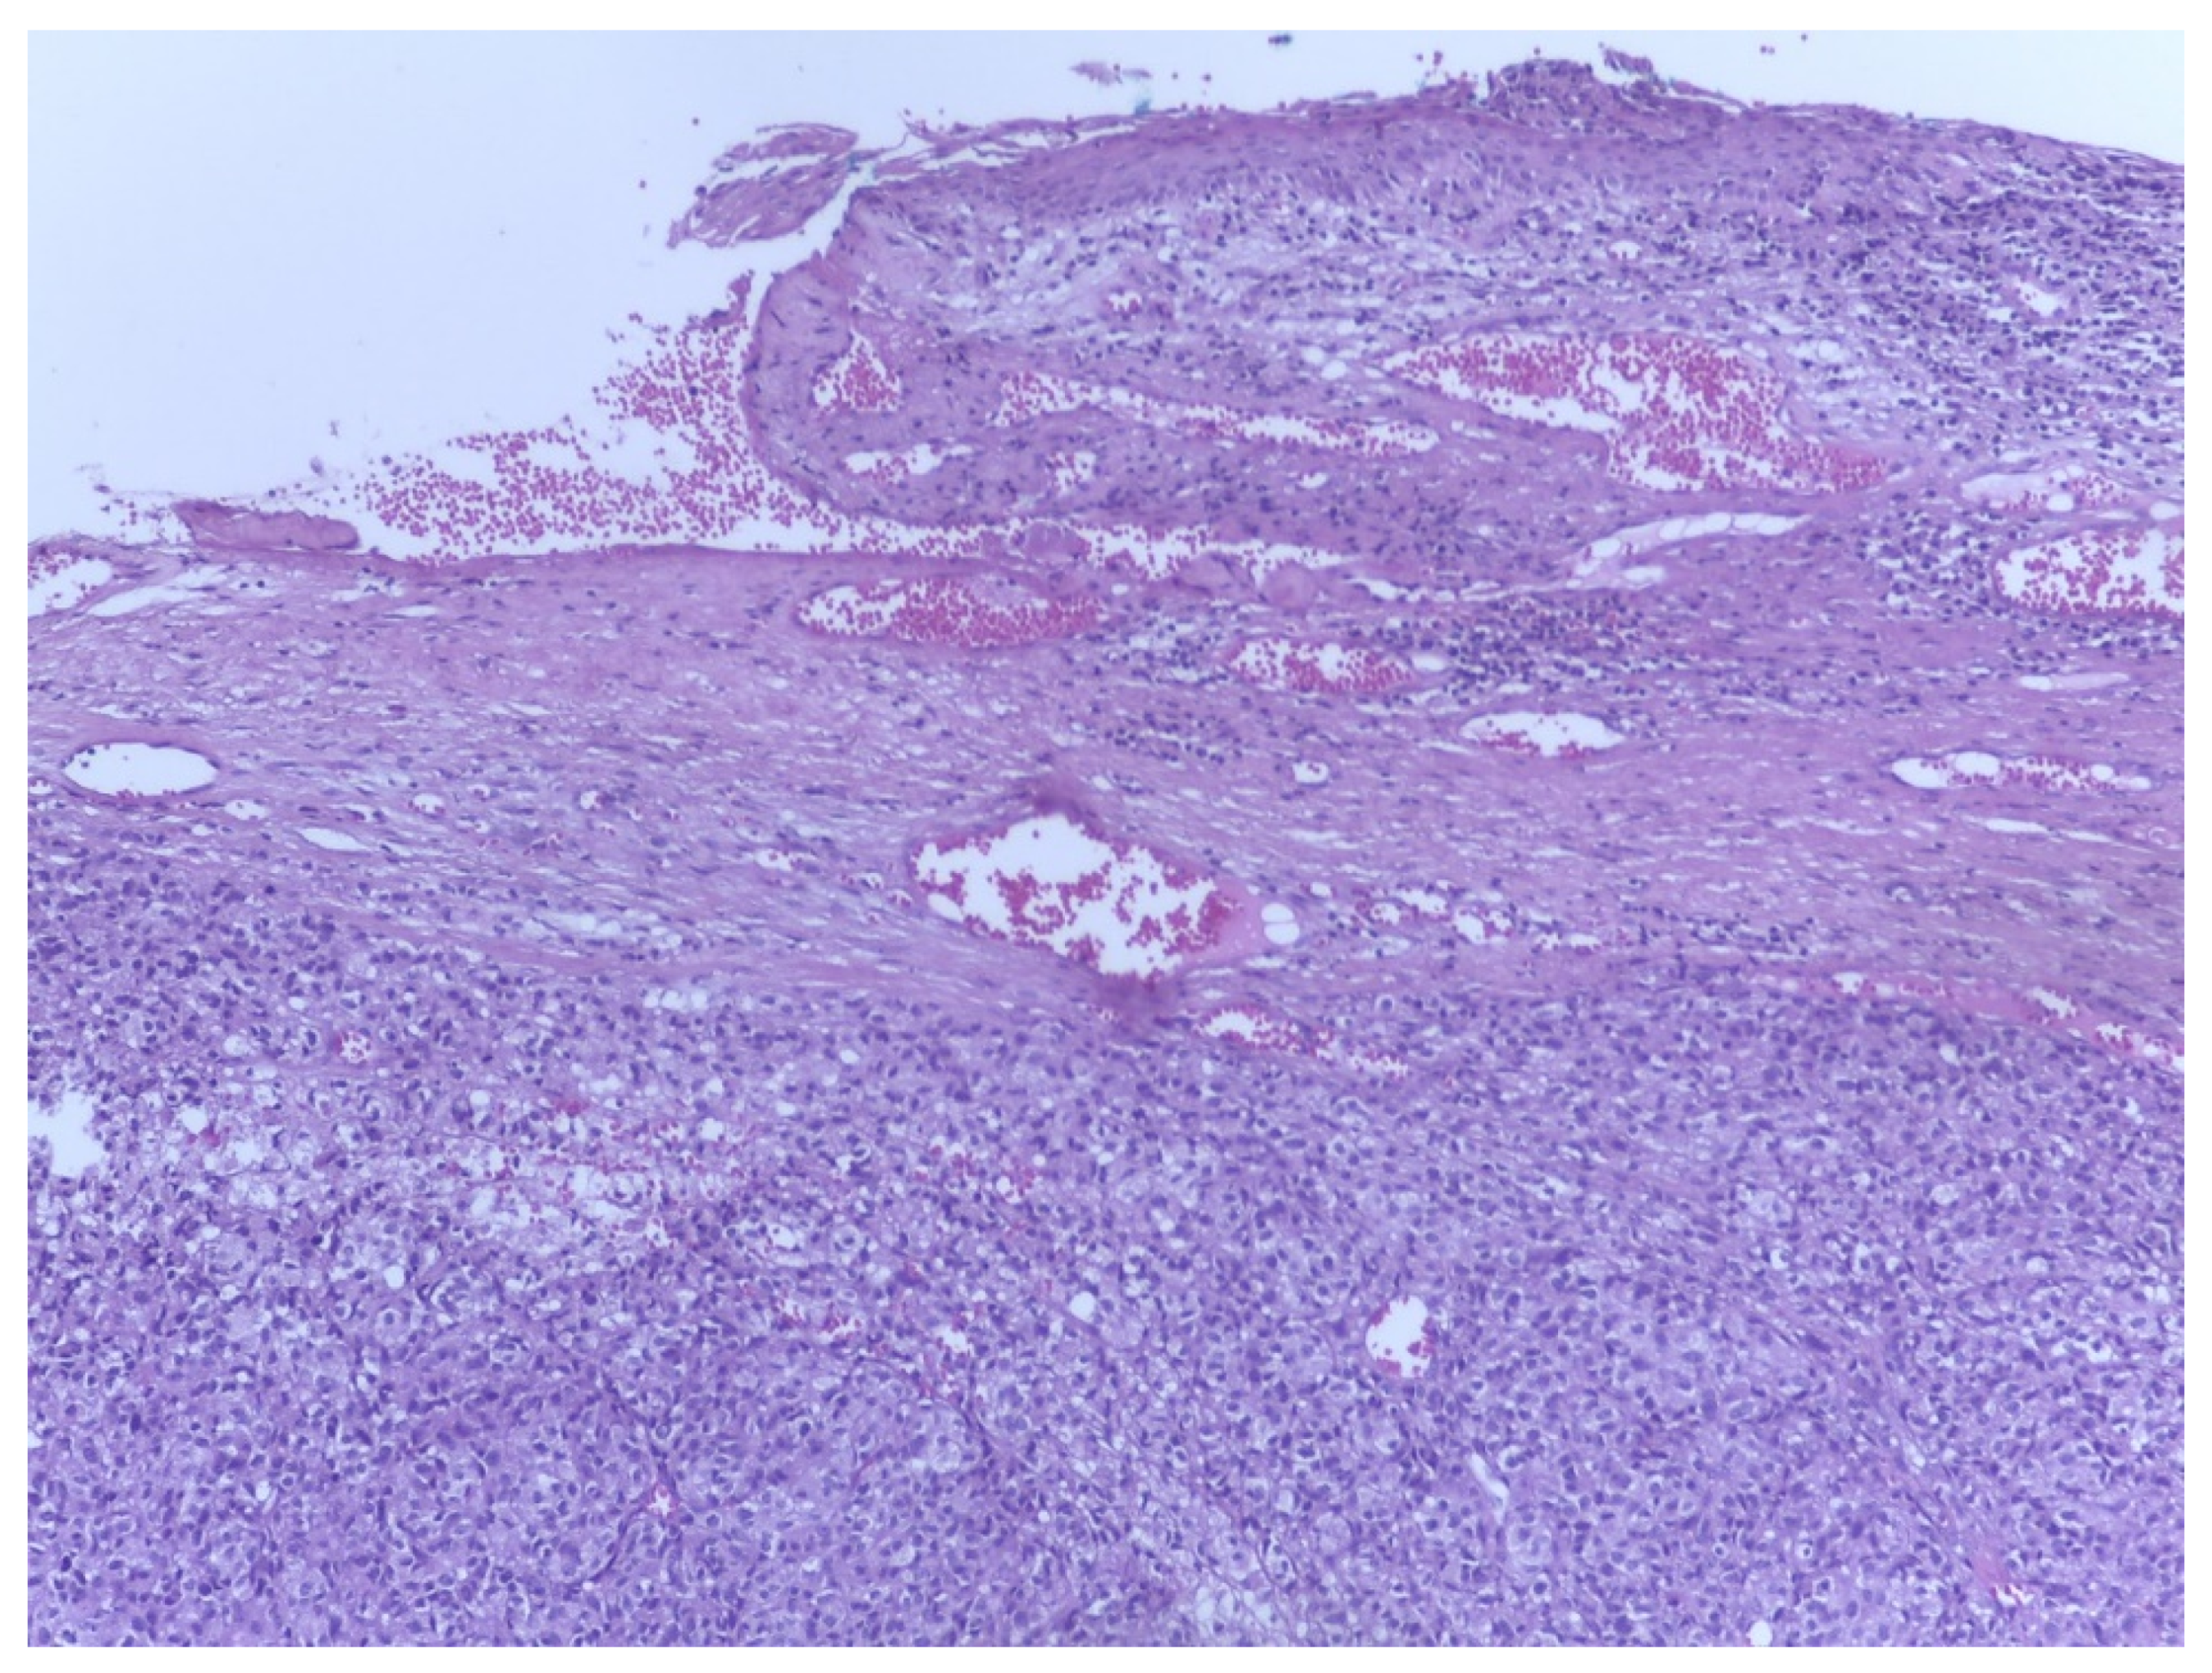

4.2. Microscopic Examination

4.3. Histological Subtypes of Melanoma